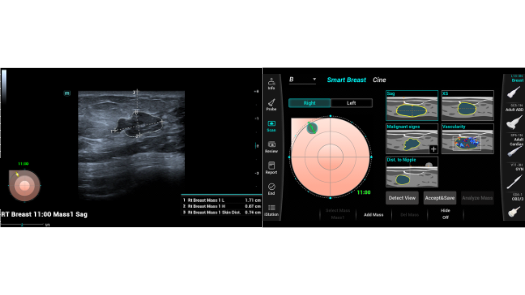

Independientemente de si lleva a cabo su rutina en hospitales o clĂnicas, o si estĂĄ perfeccionando sus habilidades en aplicaciones de diagnĂłstico por imĂĄgenes generales, atenciĂłn de la salud de la mujer o especialidades cardiovasculares, esta serie dispone de herramientas muy potentes para que se mantenga a la vanguardia.

GalerĂa de imĂĄgenes